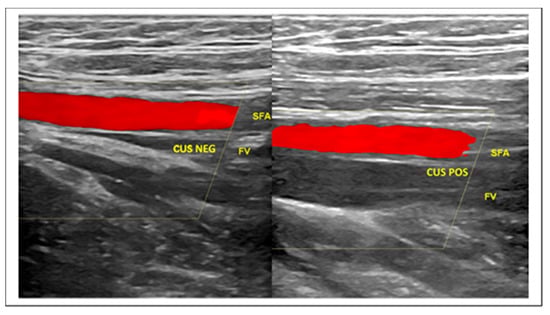

The first-line imaging test in the diagnostic management of patients presenting with clinically suspected DVT is compression ultrasonography (CUS), a powerful ultrasound biomarker [41,42,43] (Figure 4).

Figure 4.

CUS maneuver for rapid identification of DVT. (Left) The real time compression by the ultrasound probe of the femoral vessels at the thigh determines the collapse of the femoral vein. CUS maneuver negative for DVT. (Right) The same maneuver in the case of femoral vein thrombosis does not demonstrate venous collapse. CUS maneuver positive for DVT. Legend: SFA—Superficial Femoral Artery; CUS NEG—Negative for thrombosis Compression Ultrasonography; FV—Femoral Vein; CUS POS—Positive for thrombosis Compression Ultrasonography.

The ultrasound scan might include a second CUS examination after 5 to 10 days following an initial negative CUS to evaluate if a possible distal DVT has propagated to the proximal veins. Single limited, serial limited, and whole-leg CUS are the current imaging strategies for the diagnosis of DVT. Preference for one strategy over the other differs between centers and sonographers [41,42,43,44].

Due to frequent association with VTE, it could be reasonable to complete the LUS screening protocol with CUS investigation at the level of the jugular, subclavian, femoral, popliteal, and calf muscular venous segment, according to the above protocols. The addition of ultrasound venous images to the LUS protocol takes just a few minutes and is able to provide fundamental prognostic and therapeutic information (Figure 4). Finally, taking into account all the above data for the diagnosis of COVID-19 and the frequent VTE complications, the usual DVT diagnostic algorithm could be usefully modified by means of blood and ultrasound vascular biomarkers, according to a novel flowchart illustrated in Figure 5.